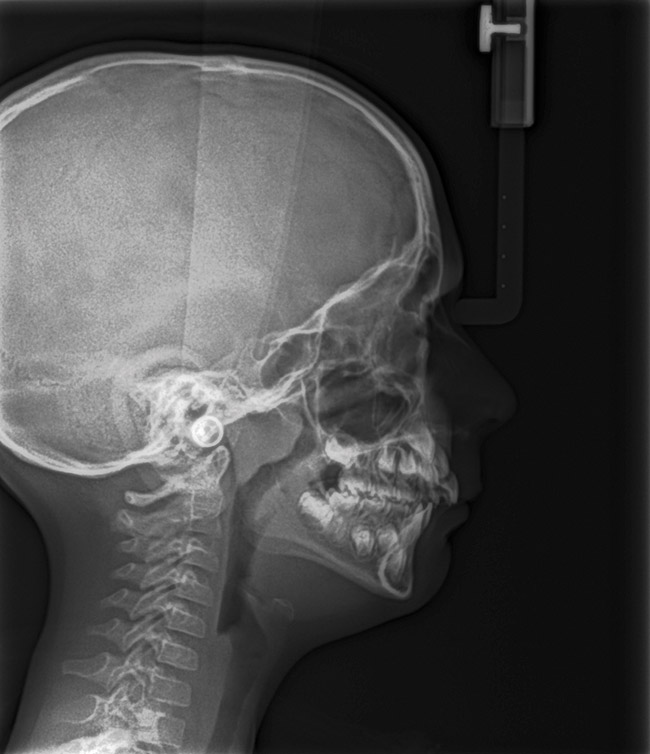

(15.) Cephalometric evaluation demonstrates significant tonsillar blockage of the airway and bimaxillary retursion.

Figure 15